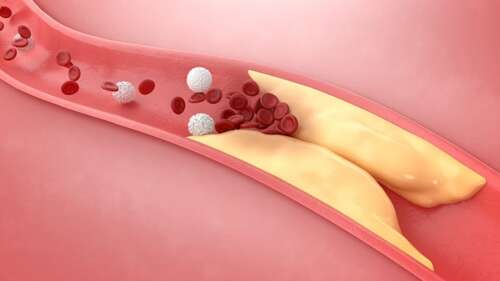

What Are the Effects of Vitamins D3 and K2 on Coronary Artery Disease?

Dr. Joseph Mercola DO - Mar 4th 2024 10:32pm EST